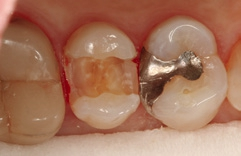

Bei dem 57-jährigen Patienten imponierte in der Routine-Bissflügelaufnahme eine Sekundärkaries an dem mit einem Gold-inlay versorgten Zahn 14 (Abb. 1). Der vitale und symptomfreie Zahn zeigte lediglich radiologisch (Abb. 2) einen Randdefekt distal sowie den Verdacht auf Karies unter dem Befestigungs- bzw. Unterfüllungszement. Nach Entfernung des Goldinlays ergab sich der Verdacht auf eine Pulpaeröffnung (Abb. 3). Klinisch war keine Blutung feststellbar, was allerdings durch die Lokalanästhesie kaschiert sein konnte. Aufgrund der Symptomlosigkeit des Zahnes und fehlender Anzeichen einer Pulpitis (fehlende Blutung) sowie einer Nekrose (erhaltene Vitalität) fiel die Entscheidung zugunsten einer Vitalerhaltung unter Beibehaltung eines engmaschigen Recalls mit Vitalitätsproben. Die Überkappung der Eröffnungsstellen erfolgte als Alternative zu Calciumhydroxid [8] mit einem Portlandzement enthaltenden Flowkomposit mit hohem pH-Wert [7,51] (TheraCal LC, Bisco, Abb. 4). Obwohl dieses Produkt hinsichtlich seiner Effektivität und Zelltoxizität nicht an ProRoot MTA (Dentsply Sirona) und Biodentine (Septodont) [42] herankommt [5,11], ist es hinsichtlich seiner Praktikabilität und der Möglichkeit des sofortigen, zügigen Weiterarbeitens konkurrenzlos. Ein vergleichbares Produkt gibt es z.B. bei Ultradent (Ultra- Blend Plus).